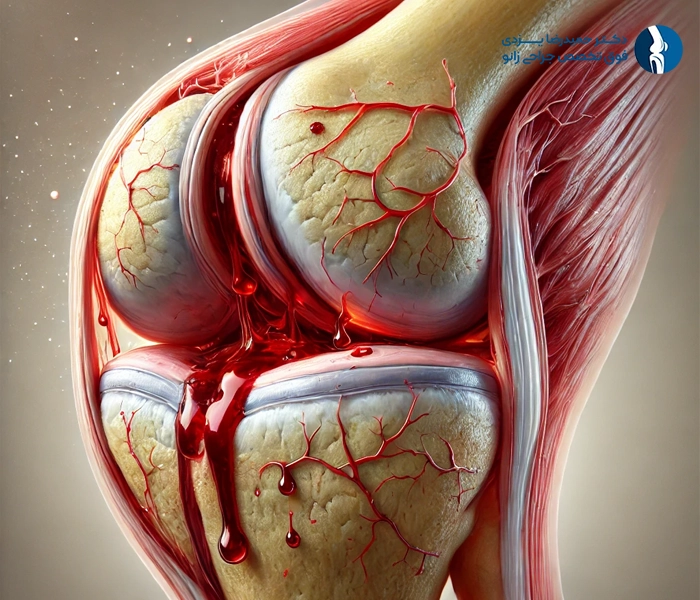

5.خونریزی داخل مفصلی (همارتروز)

خونریزی داخل مفصل زانو میتواند باعث درد، تورم و محدودیت حرکت شود. در صورت بروز این مشکل، ممکن است نیاز به تخلیه خون از مفصل باشد.